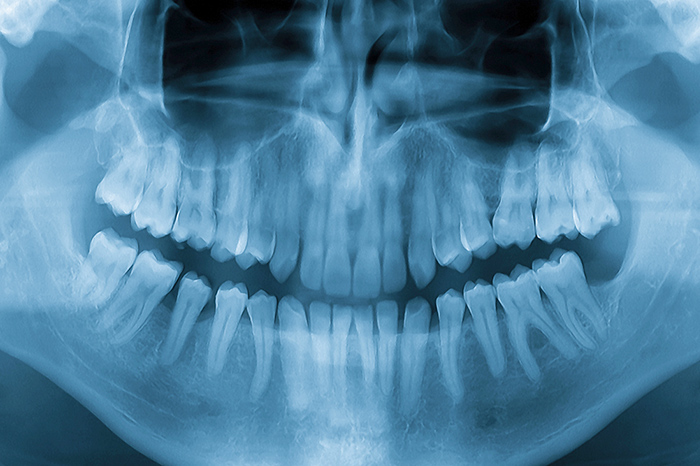

30分ほどカウンセリングにお時間をいただき、痛みがある場合は応急処置をします。その後、レントゲン写真撮影、むし歯・歯周病検査など、治療計画を立てるために必要な検査を実施します。なお、初診時はむし歯治療は行いませんのでご了承ください。